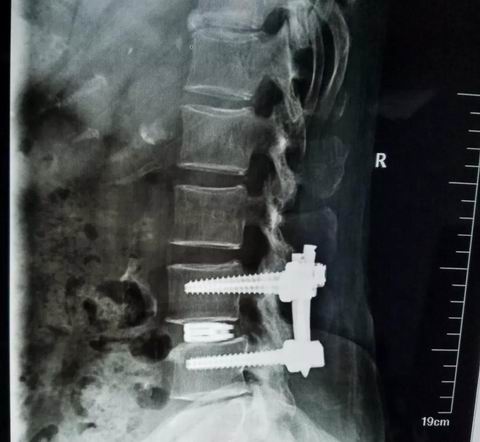

安钢总医院脊柱微创团队在通过仔细分析病人的临床资料与影像学特点后,并在患者拒绝开放手术的要求下,决定采用微创脊柱内镜下融合术preint-ELIF(Endoscopy Lumbar interbody fusion)。脊柱微创团队进行了精心地术前准备,于7月31日上午10点开始手术。手术中,王院长准确定位置管,经椎间孔镜下腰3/4椎间盘减压彻底,扩大手术通道至2厘米,通道下应用终板处理器处理终板,放置大小合适的融合器,最后结合经皮椎弓根螺钉复位脱位的腰4椎体并固定。此微创术式创伤小,术后恢复快,但手术难度大。

在经过整个脊柱微创团队3个小时的奋战后,手术圆满完成,出血量仅为传统手术的六分之一。目前,腰椎融合手术是治疗腰椎间盘疾患的主要方式,应用较多的仍是后路融合术(PLIF),这种手术虽然疗效确切、融合率较高,但需要在后背切开长约10cm的刀口,因为是直接减压,要破坏腰椎的肌肉、小关节、椎板等后柱结构,对脊柱后柱结构破坏较大,另外椎管内瘢痕增生易导致神经受压,故远期效果往往欠佳。微创脊柱内镜下融合术preint-ELIF(Endoscopy Lumbar interbody fusion),从侧路行椎间融合,不但植骨面积大,融合率高,还保留了后柱结构,避免了对椎管内结构的干扰。较传统ALIF及XLIF风险小,preint-ELIF技术简化了手术的过程,减少术中出血与组织创伤,减少术后疼痛与炎性反应导致的粘连,同时缩短住院时间并更有利于患者康复,是一项具有良好发展前景的技术,但此项技术难度较高并需要较长的学习曲线。